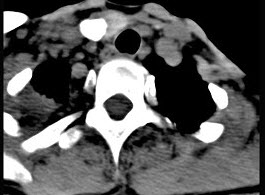

50岁女性患者,体检发现右侧甲状腺有较硬结节,CT扫描如图所示,请选择正确的描述和答案()。

A、右侧甲状腺内见稍低密度影,周边围以环形致密钙化影

B、肿块影与周围结构分界清楚

C、考虑为结节性甲状腺肿

D、考虑为甲状腺癌

E、考虑为甲状腺腺瘤钙化

A,B,E